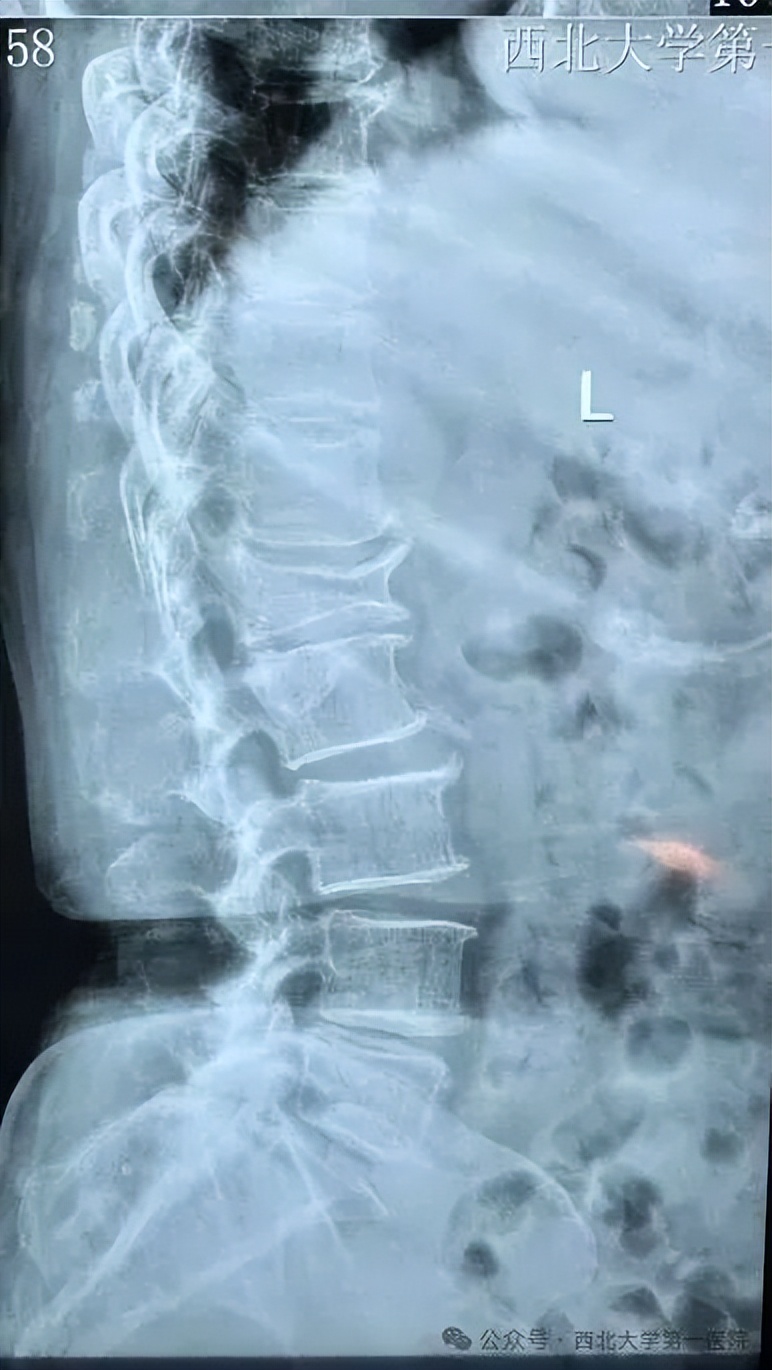

为确保手术的长期效果,该科评估远超膝关节本身,从“脊柱-髋-膝-踝”整体评估力线。根据影像学检查,分析了患者的脊柱-骨盆-膝-踝整体力线联动体系,确认其膝内翻畸形源于关节内的软骨磨损,而非腰椎或骨盆等上游问题引发的代偿性畸形。